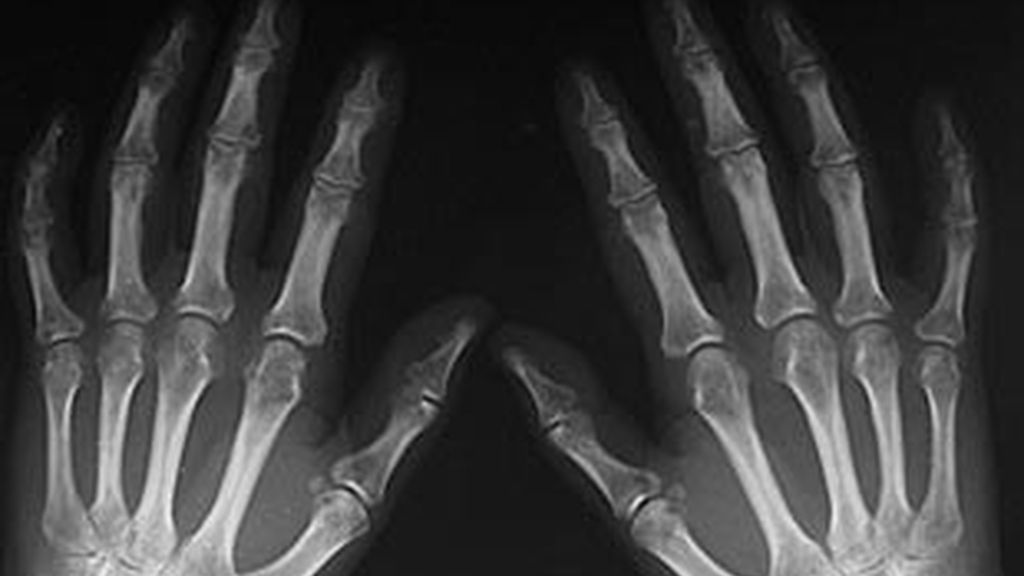

¿Por qué el dedo anular de los hombres es tan largo?

Como consecuencia de la testosterona y el estrógeno, los hombres tienen los dedos anulares más largos que los índices. La diferencia de longitud de los dedos ha sido relacionado repetidamente con actitudes en los humanos como la agresividad, la habilidad musical o la orientación sexual. Ahora también se ha vinculado a enfermedades como el autismo, la depresión, los ataques cardíacos o el cáncer.